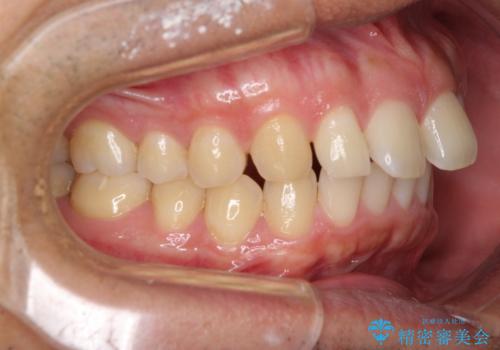

インビザライン開始前に奥歯の咬み合わせを変える補助装置は幾つかあります。

咬み合わせの強さや下顎の歯列の状態などによって、最適な補助装置を選択しています。

インビザライン単独で咬み合わせを改善することもできますが、治しきれない可能性が高いため、事前に補助装置で治しておくことは、治療の仕上がりの点で非常に重要となります。